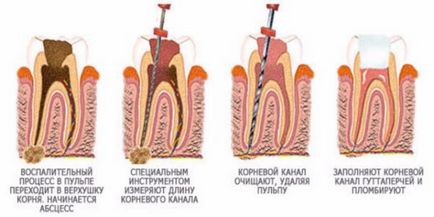

Infecția în canalele dentare

Inflamația canalelor este un alt motiv pentru care dintele dăunează în timpul depresiei. Dentiștii sugerează îndepărtarea nervului la pacient destul de rar. Desigur, doriți să vă păstrați dintele, dar nimeni nu dorește să sufere durere neplăcută. Înainte de a începe medicul, trebuie să îndepărtați sigiliul vechi și să curățați canalele. Sunt de diametre diferite, iar pentru extensia lor doctorul folosește ace spirală. Canalele sunt curățate și dezinfectate. Se usucă și se umple materialul. Atunci când canalele dentare sunt prost curățate și prost închise, infecția se dezvoltă.

Procesul de apariție a pulpitei